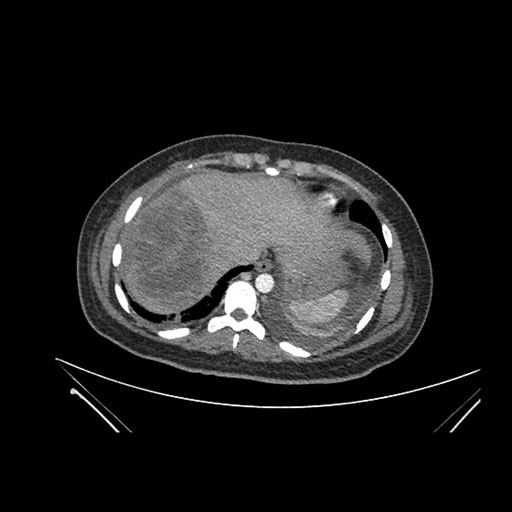

Imaging Analysis

Look through the patient's CT scan to identify any areas of concern for the necessary procedure.

Axial Venous

Based on initial findings, which issue(s) would you be most concerned about?